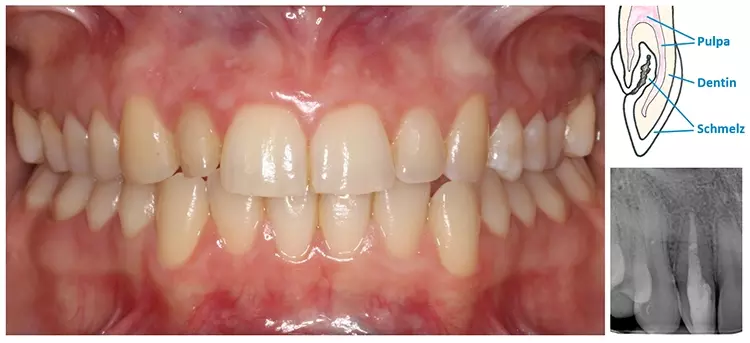

Ihr Videofilm dokumentiert die Rehabilitation des frakturierten Frontzahns 12 sowie der verloren gegangenen Vertikaldimension aufgrund erosiven Zahnhartsubstanz-Verlustes bei einem 75-jährigen Patienten. Die Behandlung wurde in 3 Bisshebungsphasen gegliedert. Gezeigt wurde die digitale Herstellung einer Polycarbonatschiene sowie eines non-prep Langzeitprovisoriums aus Hybridkeramik.Während der Tragephase der Schiene können sowohl Daten für die finale Versorgung gesammelt sowie Änderungen hinsichtlich Phonetik, Ästhetik oder Funktion vorgenommen werden. Durch die Hinterlegung der Datensätze sind auch Modifikationen bei der Gestaltung des LZP sowie der späteren keramischen Versorgung jederzeit möglich.

Aini, Awiszus, Bornmann